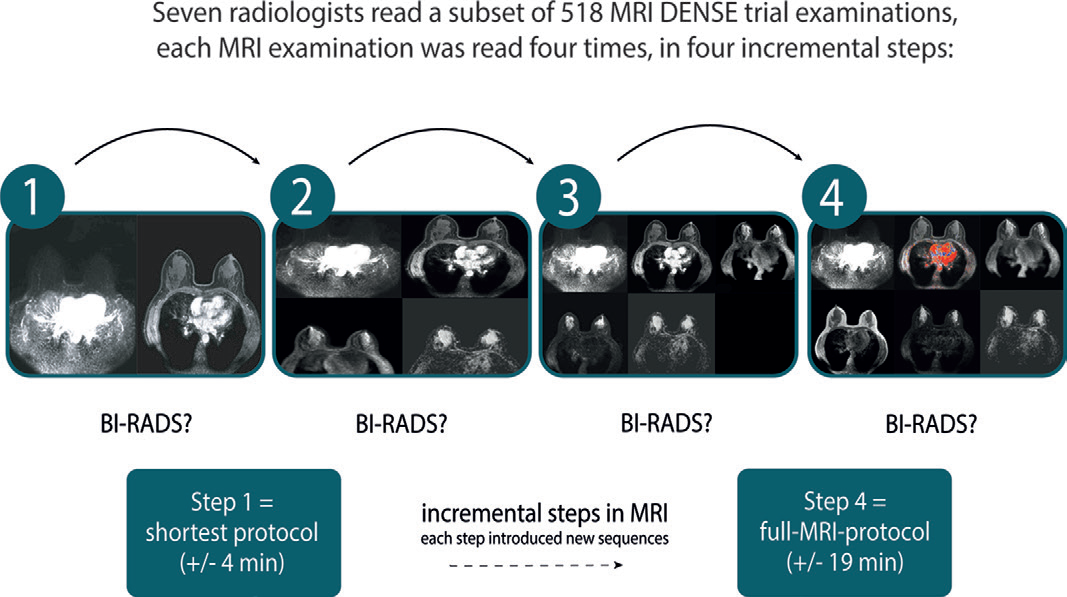

本研究基于 DENSE 试验(NCT01315015),旨在通过多阅片者(7 名资深乳腺影像专家)对比分析4 种递增式 MRI 协议的诊断效能,核心目标是:确定维持高敏感性和特异性的最小化扫描方案。

2. 四步递增式 MRI 协议设计

| 步骤 | 序列构成 | 扫描时间 | 核心技术要点 |

|---|---|---|---|

| Step 1(极简协议) | 双动态 T1 加权序列:- 高时间分辨率 - 低空间分辨率(动态监测对比剂早期分布)- 低时间分辨率 - 高空间分辨率(病灶定位)- 对比剂注射后 120 秒内采集 | 约 3.5 分钟 | 仅保留对比剂早期强化信息,聚焦 “快进快出” 的恶性特征 |

| Step 2 | Step 1 + 扩散加权成像(DWI) | 约 8.5 分钟 | b 值设置:≥800 s/mm²,检测水分子受限扩散 |

| Step 3 | Step 2 + T2 加权成像 | 约 12.5 分钟 | 脂肪抑制 T2WI,评估病灶信号特征(如囊性 / 实性) |

| Step 4(全参数协议) | Step 3 + 全序列:- 非脂肪饱和 T1 预扫- 120 秒后延迟期动态相- 增强曲线动力学分析(Type I/II/III 型) | 约 18.5 分钟 | 完整涵盖病灶形态、血供、代谢特征 |

3. 阅片与分析方法

- 盲法阅片:7 名阅片者(均有≥16 年乳腺 MRI 经验)独立按 4 步阅片,每步记录 BI-RADS 评分(1-5 类),不告知病例真实性质。